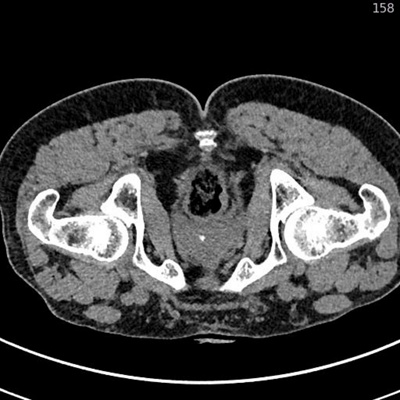

Canalis1

CT-gesteuerte Infiltration des Nervus pudendus im Canalis pudendalis (Alcock-Kanal) bei Pudendus-Neuralgie

Canalis2